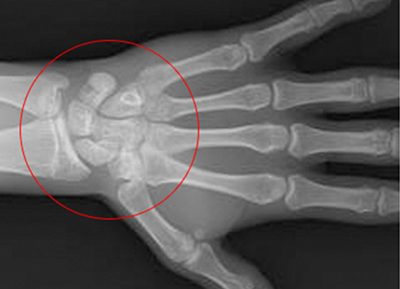

손으로 확인하는

우리아이 성장판 검사

아이의 나이 만으로 발육 정도를 파악 할 수 있지만 동일한 나이임에도 불구하고

개인적인 성숙도가 많이 다르기 때문에 정확한 성장 정도를 판단하기 위해 성정판 검사를 통해 교정의 적절한 시기를 결정합니다.

• 1

열려있는 성장판

• 2

닫혀가는 성장판

• 3

완전히 닫힌 성장판

성장판이 닫혀 있어도 치아 교정이 가능하지만 골격적인 부분에 대한

교정이 이루어 지려면 성장판이 닫히기 전에 교정을 시작하여야 더 좋은 효과를 기대할 수 있습니다.